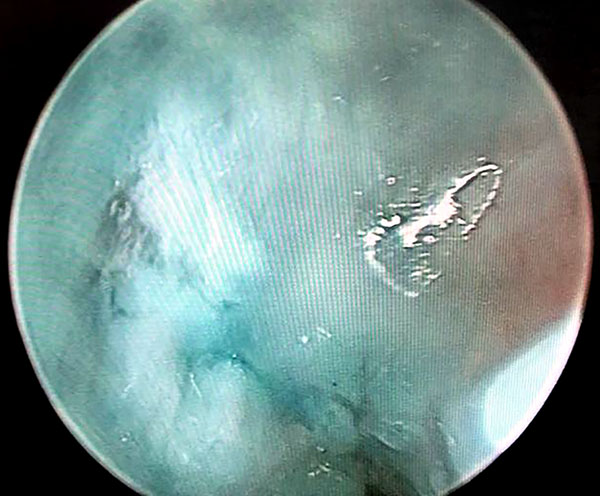

Luego por articulación radiocarpiana, se debrida y estimula el ligamento escafolunar; y si lo amerita realizamos radiofrecuencia del mismo previo a Capsulodesis. Terminado este paso, realizamos la técnica modificada de Mathoulin. Se realiza el pasaje de una sutura prolene 2.0 por medio de una aguja intramuscular desde la cápsula dorsal 1 cm proximal al portal 3/4 y 1 cm cubital (figs. 1 a 4).

Figuras 1 a 4: Muestran visión por portales 6R con ingreso de agujas con hilos desde capsulo hacia el ligamento escafolunar.